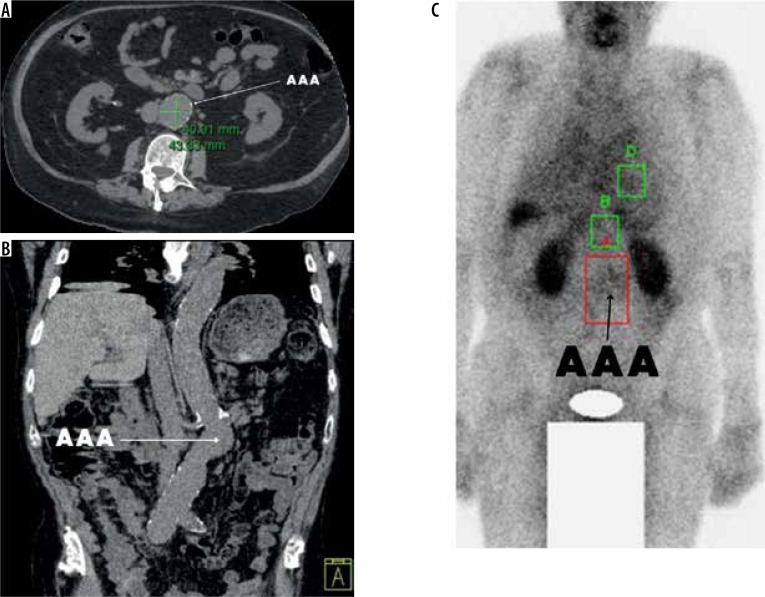

Material and methods: A pilot study was performed to evaluate patients with small asymptomatic AAA. The equipment used was a Symbia T2 (Siemens, Germany), with radiolabeled 99mTc-HYNIC-CCR2-L. The SPECT uptake and activity were assessed and counted based on the region of interest (ROI), with nonparametric statistics being employed to compare the aneurysms site, left ventricle (Control 1) and regions with a nondiseased aorta (Control 2).

Results: The three patients were male (100%) (mean age 81 years, and mean AAA maximum diameter of 40 mm, SD 3 mm). All patients tolerated the studies well. Images were obtained at one, two and four hours. The ROI mean value of the aneurysm site was 37,783 (SD 11,890), compared to the left ventricle (Control 1) 16,779 (SD 4397) (p-value = 0.0001); ROI for the nondiseased aortic region (Control 2) was significantly lower, 12,520 (SD 2141) (p-value = 0.0001).

Conclusions: Significant differences of CCR2 expression SPECT were found in the AAA site compared to the left ventricle and nondiseased aortic segments. The introduction of well-designed longitudinal studies with nuclear imaging modalities may assist in the molecular characterization of aneurysmal and rupture prediction.